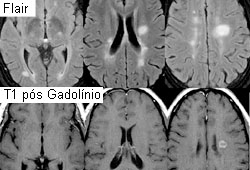

A RNM cranioencefálica com gadolínio é usada quando se considera o diagnóstico de esclerose múltipla. Deverão ser realizadas uma punção lombar e análise do líquido cefalorraquidiano (inclusive contagem diferencial de celularidade, cultura e sorologia), juntamente com um teste de potenciais evocados, se houver suspeita de esclerose múltipla. A punção lombar e a análise do líquido cefalorraquidiano devem ser realizadas se houver suspeita de encefalite e tiver sido descartada a presença de uma lesão com efeito de massa no cérebro. Uma TC do tórax será útil para diagnosticar um timoma, após uma radiografia torácica.[Figure caption and citation for the preceding image starts]: Ressonância nuclear magnética (RNM) com recuperação da inversão atenuada de fluido (FLAIR) e agente de contraste gadolínio, exibindo lesões típicas observadas na esclerose múltipla (EM) nas regiões periventriculares.Do acervo pessoa de Lael A. Stone, Mellen Center for MS Treatment and Research, Neurological Institute, Cleveland Clinic Foundation; usada com permissão [Citation ends].